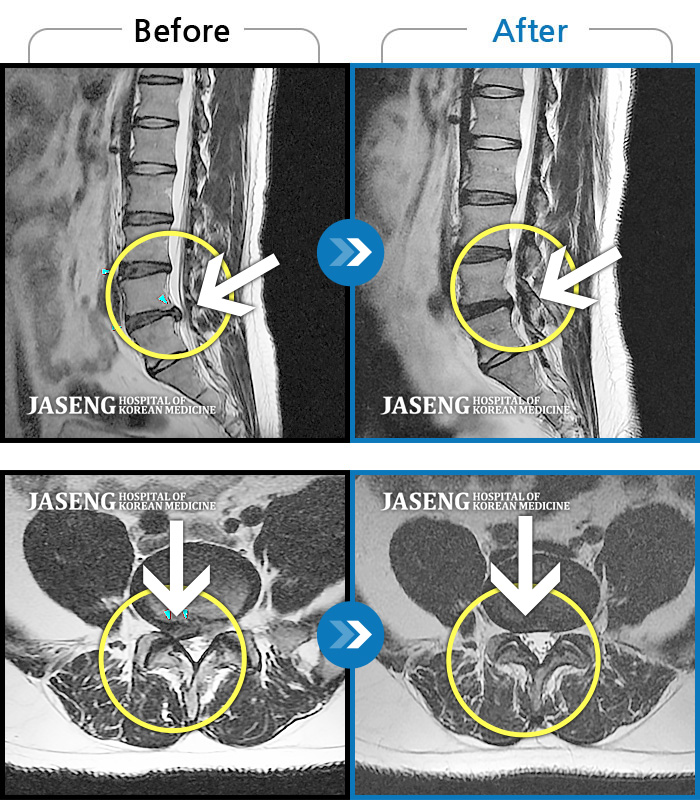

MRI 치료사례

허리디스크

보라매 · 빈상은 원장

엉치에서 좌측 다리까지 통증, 저림으로 움직일 수가 없어요.

촬영시기

2024.08.03 ~ 2025.05.02